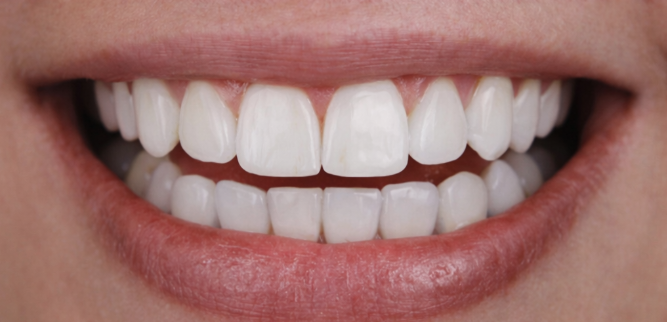

- ✔️ Cosmetic Dental Treatments